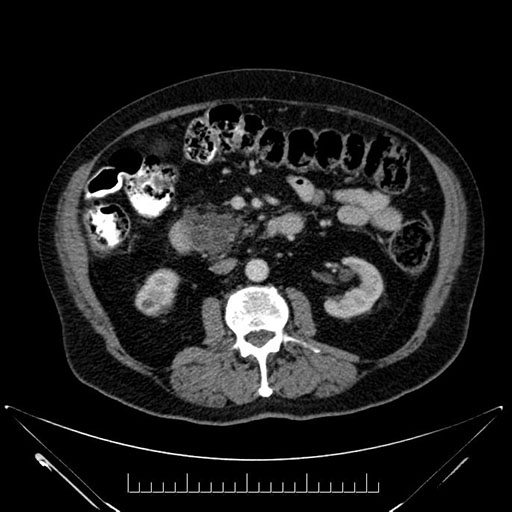

Axial - 3 months prior